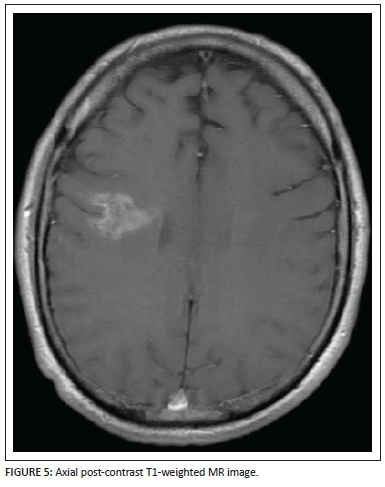

Coronal (Figure 4) and axial (Figure 5) post-gadolinium T1-weighted sequences demonstrate the patchy enhancement of the major portion of the lesion except for the focal areas of necrosis centrally within the lesion bed. The enhancing vessel is well demonstrated, extending from the pial surface through the centre of the lesion. Subtle brush-like vascular enhancement is also seen in the contralateral centrum semiovale white matter.